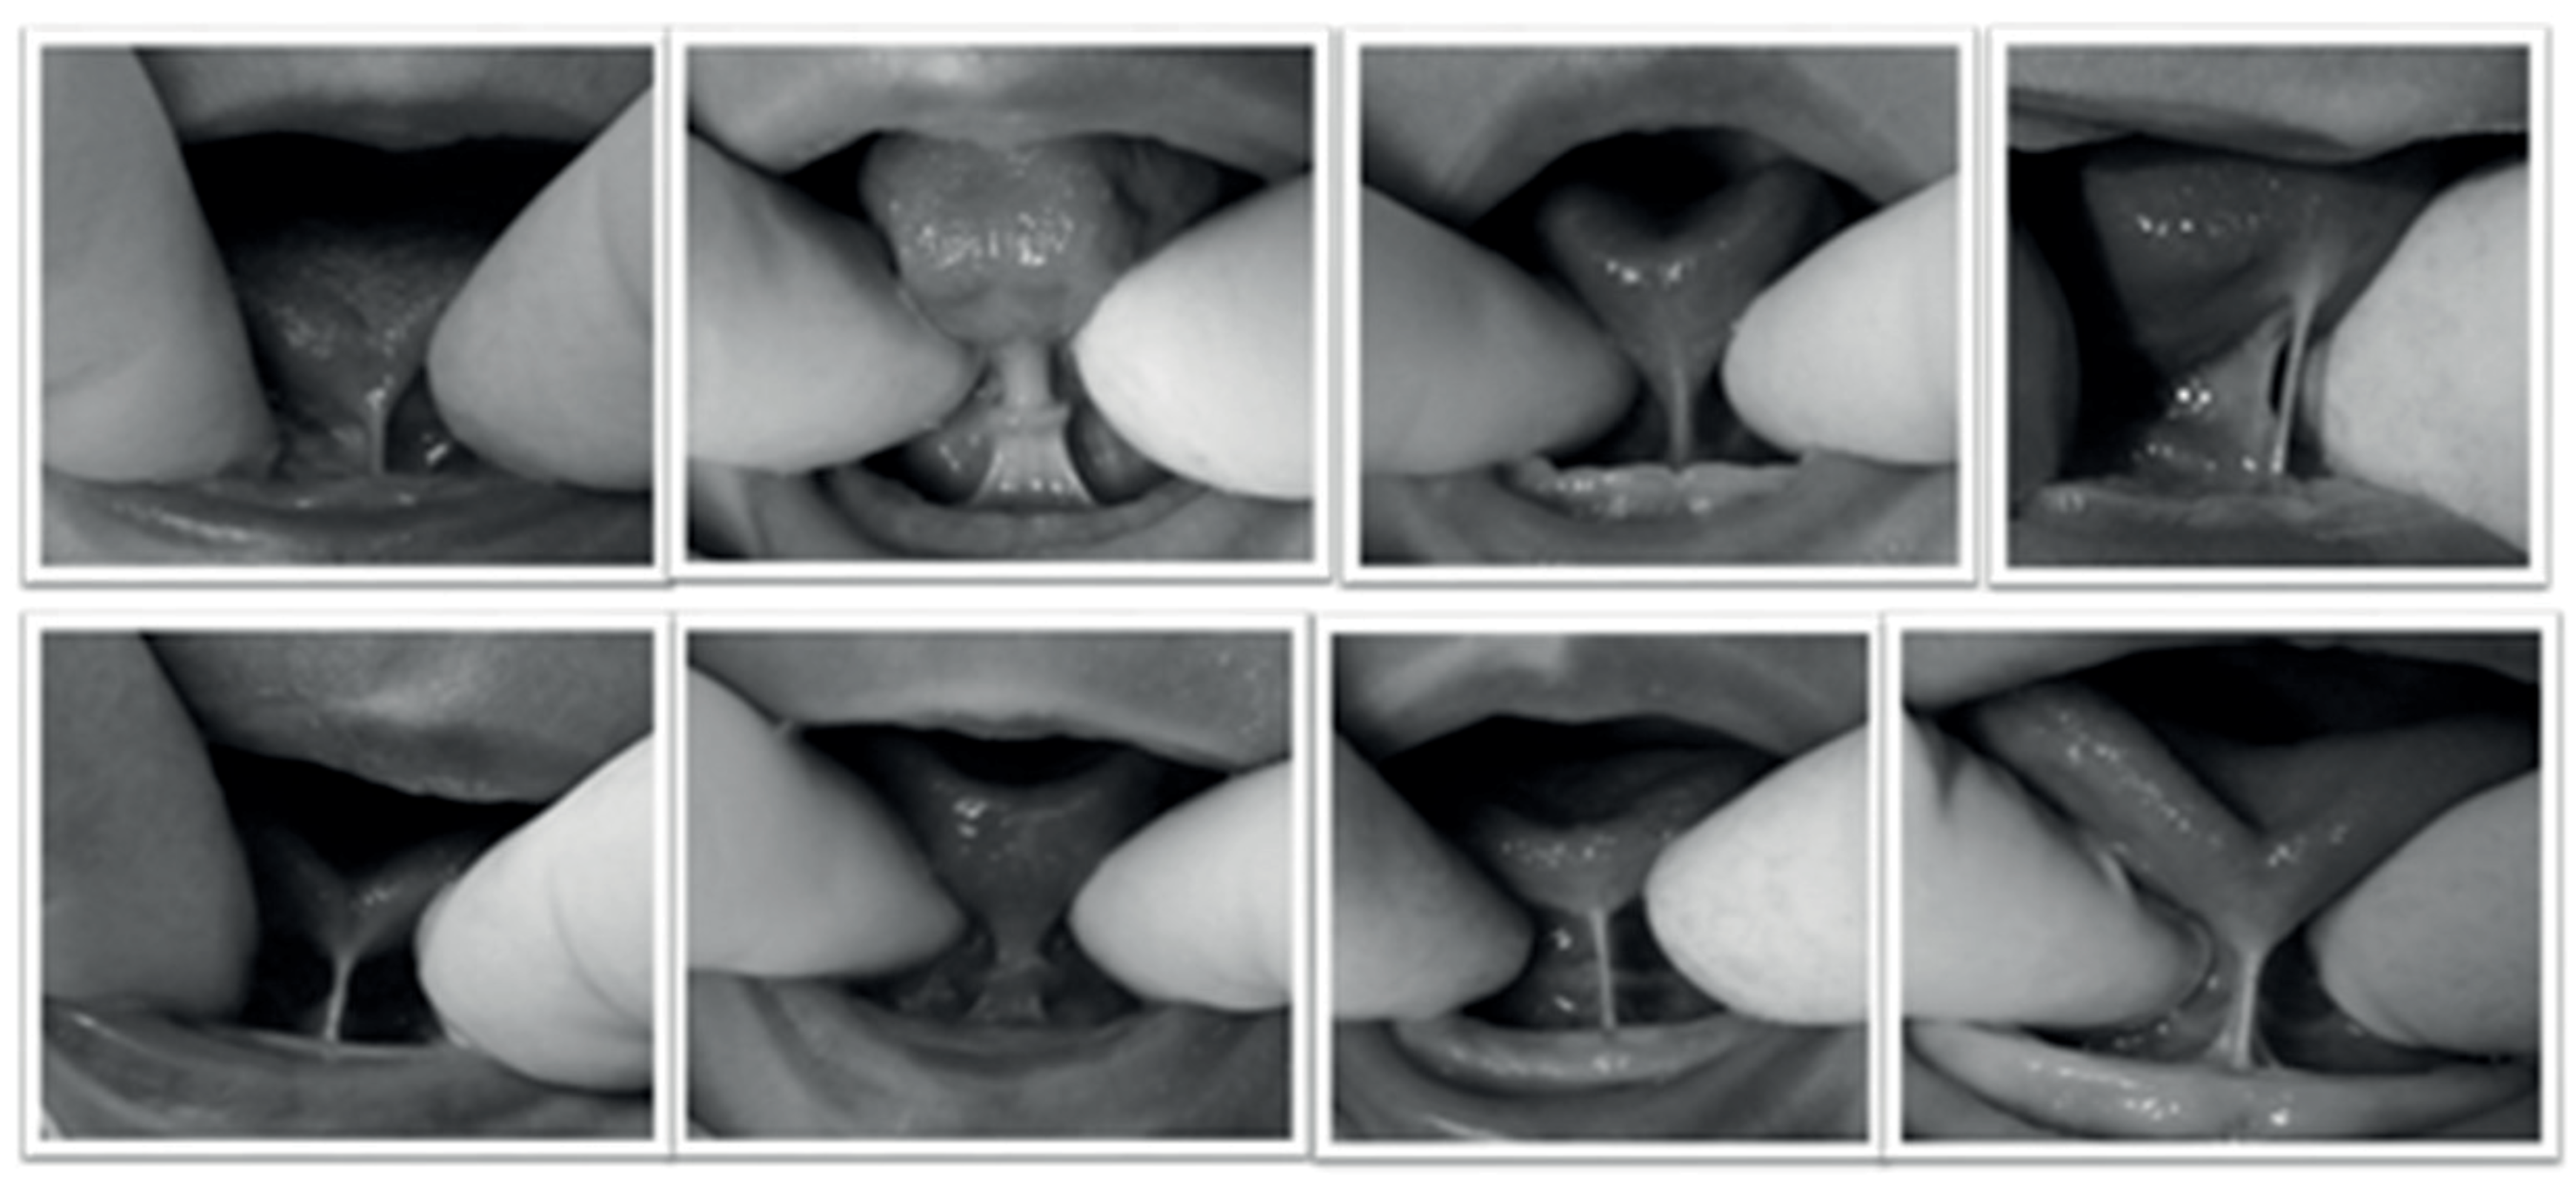

![]() |